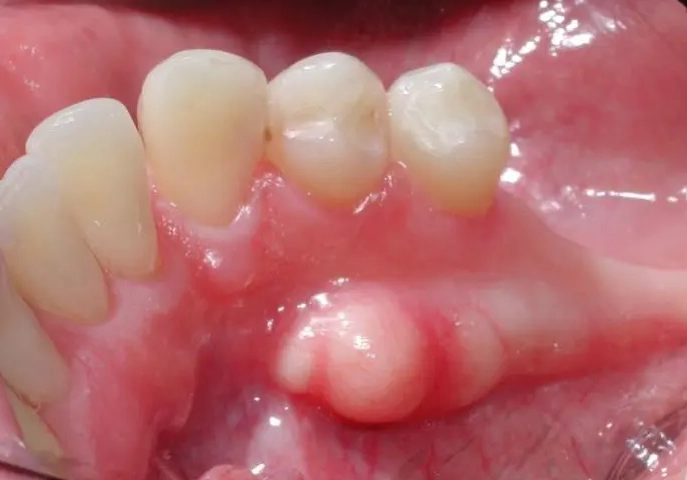

Fibroma

This is the body's overzealous response to chronic irritation. If you have a habit of chewing on your cheek, a rough tooth, or an ill-fitting denture rubbing in the same spot, your body might lay down extra fibrous tissue as a “callus.” The result is a fibroma. What it feels/looks like: A firm, smooth, pink lump. It's like a little dome-shaped knot of scar tissue. It's anchored down and doesn't move much when you push it. Completely benign and very, very common.